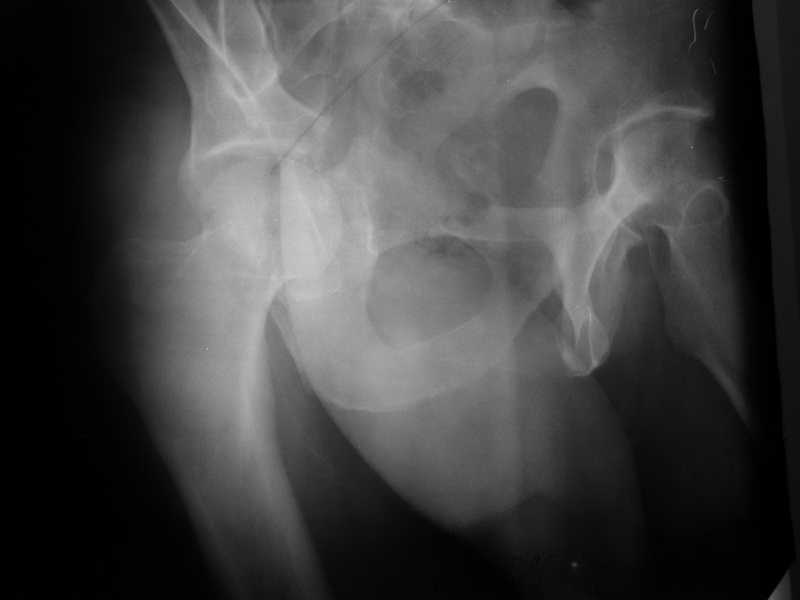

Yordan! In this case position of bone fragments is quite good. We

Sending exampl pict.